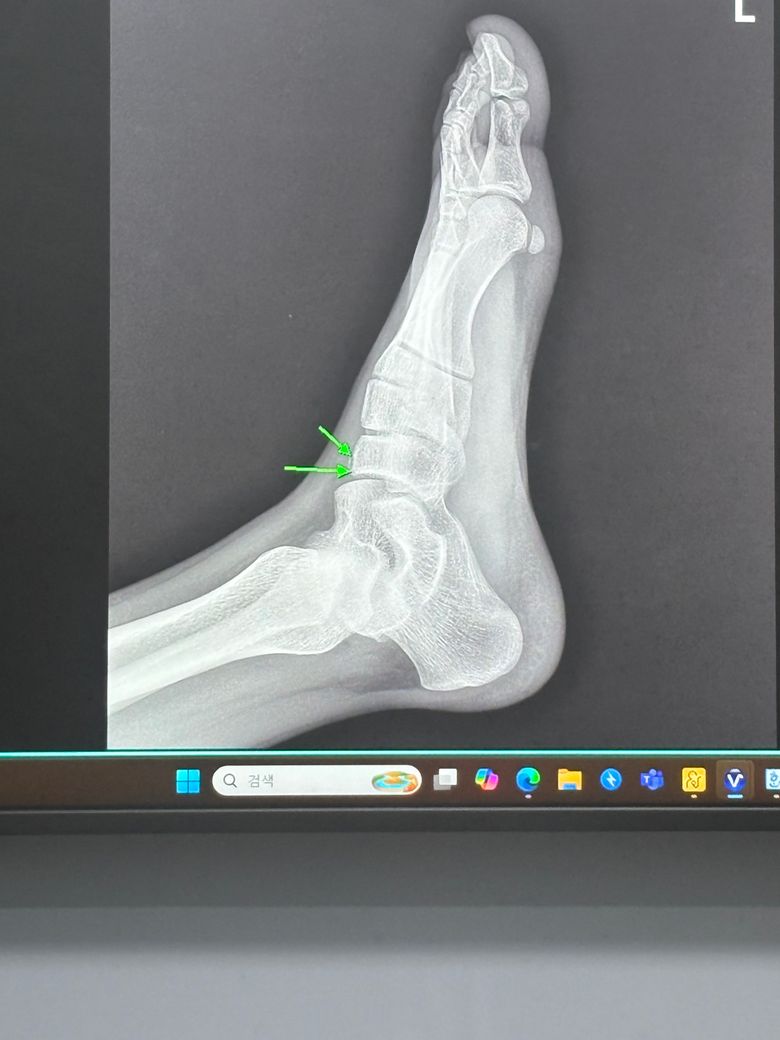

발등뼈 골절이라는데 깁스를 얼마나 해야하나요?

계단에서 뛰다가 넘어져서 발등뼈가 골절이 됐는데 반깁스 하면서 2~3일에 한번씩 물리치료를 받으러 가는데 깁스를 얼마나 해야하는지 궁금하고

몇주가 지나야 뼈가 붙을까요?

• 1번 째 사진

사진상으로는 심하지 않아 보입니다.

8주 정도 기브스 하시면 충분히 붙을 듯 합니다.